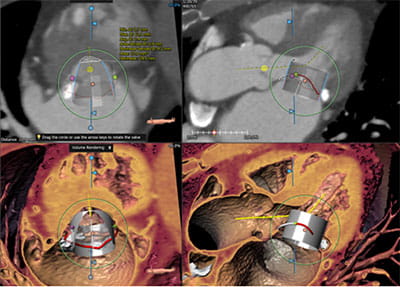

• High volume program with daily case averages of 10 CMR studies and 25-35 cardiac CTAs (50% coronary CTA, 30% structural, 20% other). Broad case complexity, including CAD, structural heart pathologies, congenital heart disease,  and implantable devices. Routine use of cutting edge technology, including T1/ECV mapping, quantitative perfusion, free-breathing CMR exam, artificial intelligence based CT analyses, CT-FFR, structural planning and simulation.